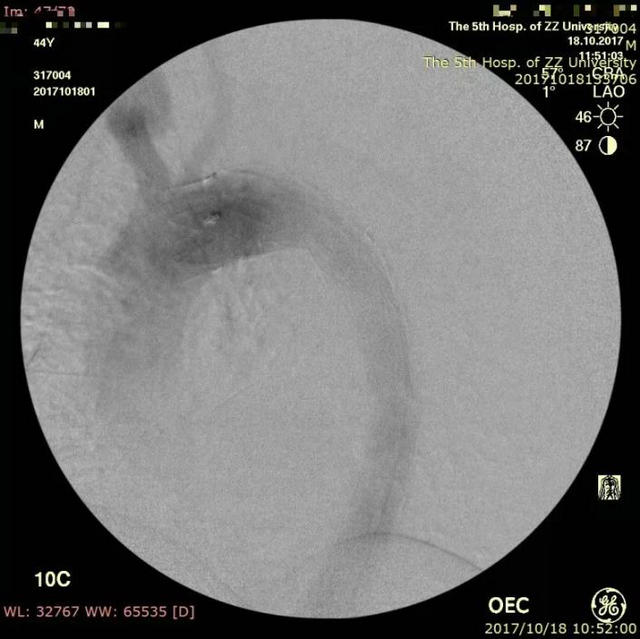

近日,郑州大学五附院血管外科就成功为一位累及左锁骨下动脉的病人开展了这项技术,取得了很好的效果。这是一位44岁的中年男性,突发腰背部疼痛,曾在当地按泌尿系结石进行体外碎石治疗,治疗后疼痛仍不缓解,再查CTA提示主动脉夹层,随即急诊转入进一步治疗。主动脉CTA显示Stanford B型夹层,但夹层累及左锁骨下动脉,如果不封堵该动脉则存在夹层继续进展的较大可能,而封堵了该动脉则可能导致头颅和左上肢的缺血症状,而且患者年轻,保留左锁骨下动脉的必要性大。经过科室的充分术前讨论,最后决定对该患者行“胸主动脉夹层覆膜支架腔内隔绝术,左锁骨下动脉原位激光开窗并支架置入术”,手术由王兵教授和崔文军副主任医师亲自操刀,手术成功,按原定计划顺利完成,用时不到2小时。术后患者恢复良好,腰背部疼痛消失,左上肢血供良好,肱动脉、桡动脉搏动有力,无头晕等不适发生,复查主动脉CTA提示支架位置、形态良好,夹层隔绝良好,左锁骨下动脉支架通畅,近期即将顺利出院。

▲ 主动脉覆膜支架放置后左锁骨下动脉不显影